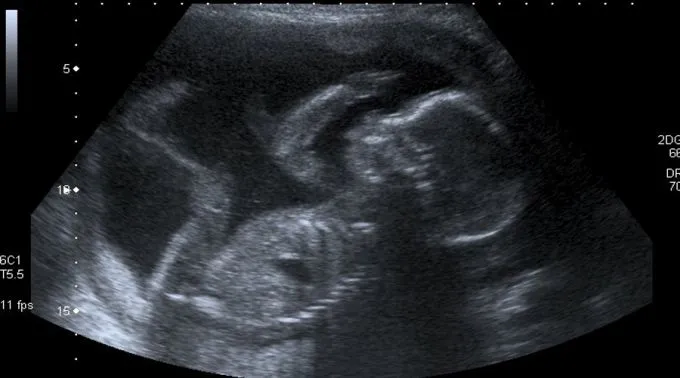

“Conclamamos os católicos e todas as pessoas que desejam um país democrático, pacífico e protetor da vida a se posicionarem contrários ao que está sendo proposto através desta medida judicial. Por ela, agride-se a vida, permitindo o aborto até doze semanas de gestação”, expressam os Prelados do Regional Leste 1 da Conferência Nacional dos Bispos do Brasil (CNBB).

Esta ADPF foi proposta pelo Partido Socialismo e Liberdade (PSOL) a fim de permitir a realização do aborto no Sistema Único de Saúde (SUS) até 12 semanas de gestação, bastando apenas o consentimento da gestante.